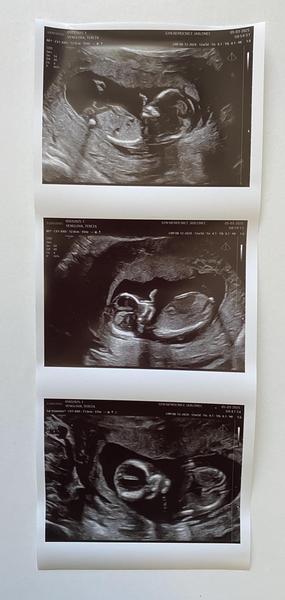

Pohlaví dítěte z ultrazvuku. Poznáte?

@martina1317 moc děkuji! On mi totiž každej tvrdí, že tý trojfotce na tom prvním obrázku je vidět pindík, ale podle mě je to nožička...

Dobrý den. Na ultrazvuku byl vidět ,, pindík, vrchem a stal🙈 Doktor řekl že tipuje kluka a za 3 tydny to pry bude vidět líp. Mam doma 4 holky🙈🤣 nepoznáte to Podle hrbolku nějakého? 🙈

Bude to krasne miminko…. Pahorek neni videt…